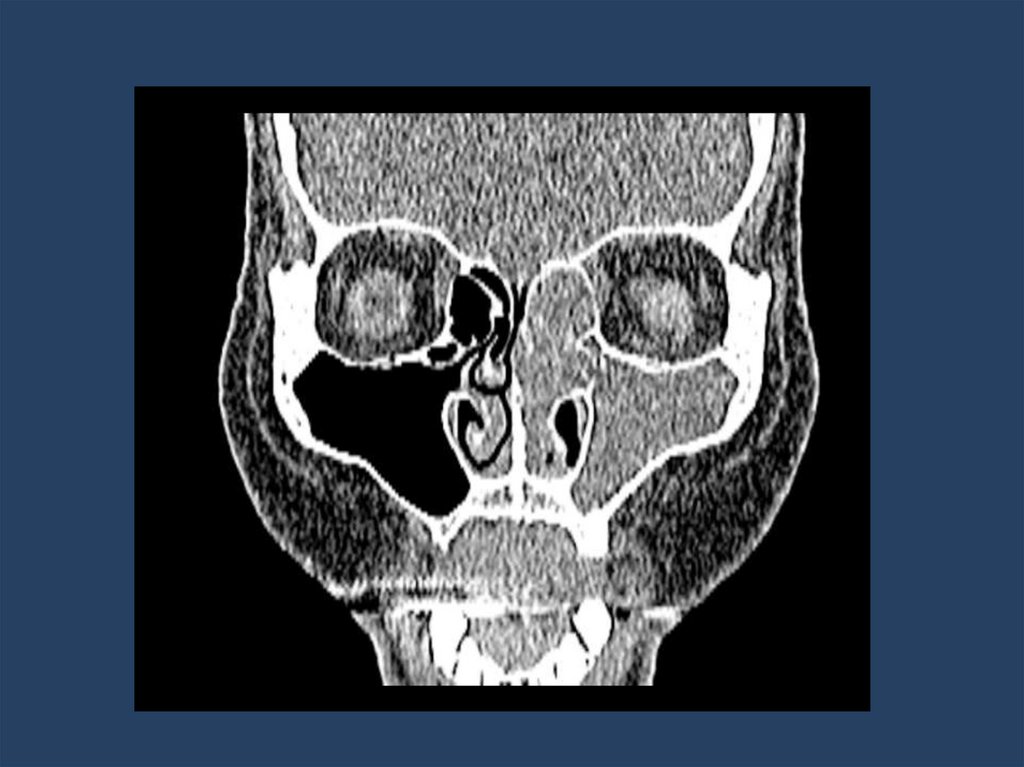

2. Лучевая диагностика:

Компьютерная томография (КТ) — метод выбора.

– Позволяет оценить костную деструкцию.

– Определяет точную локализацию и распространенность процесса.

– Характерные признаки: одностороннее затемнение пазухи, гомогенное образование

мягкотканной плотности, иногда с очагами обызвествления. Важный признак — симптом

"контралатерального отклонения" перегородки носа.